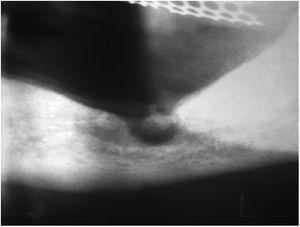

La exploración física mostraba una región perimandibular izquierda edematizada e indurada al tacto, con un área de retracción cutánea submandibular (fig. 1). En dicha zona deprimida se apreciaba una ulceración de 0,5 cm de diámetro por la que rezumaba un exudado serosanguinolento y en cuyo extremo distal presentaba una pápula carnosa excrecente, de superficie lisa y muy eritematosa.

Fig. 1.--Depresión cutánea con signos inflamatorios locales en la zona submandibular izquierda.